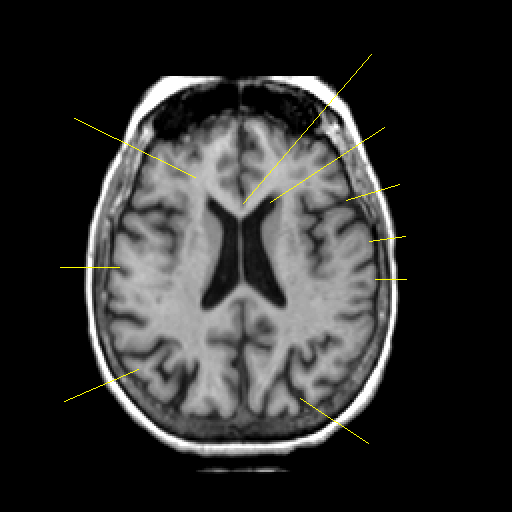

T1-weighted structural MR: Slice 32

Slice 32

Pointers

Labeled